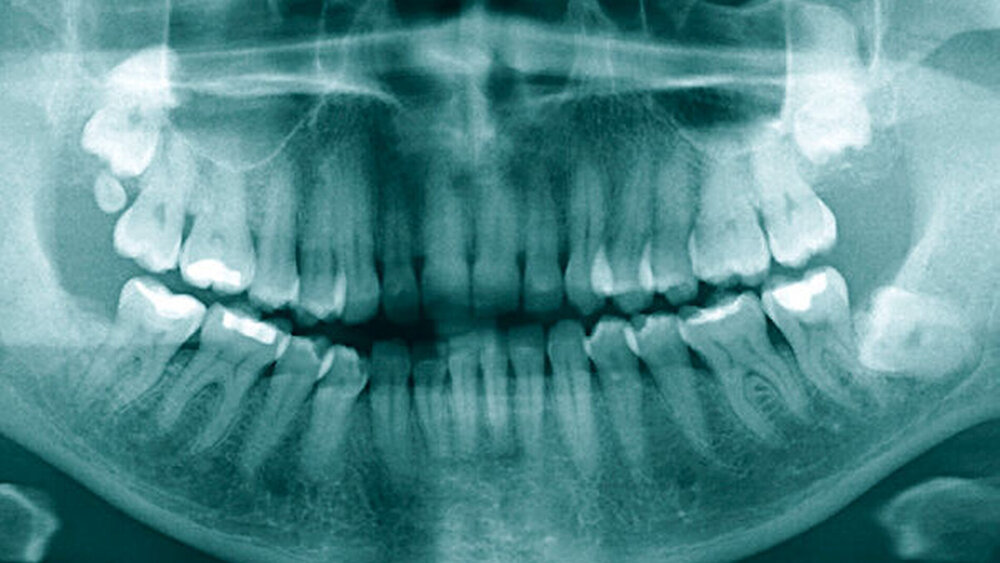

Eine 43-jährige Frau stellte sich vor über einem Jahr mit einer persistierenden vollständigen Anästhesie und Parästhesien der rechten Unterlippen-Kinnregion bei Zustand nach Osteotomie des Zahnes 48 in der Klinik und Poliklinik für Mund-, Kiefer- und Gesichtschirurgie der Universitätsmedizin Mainz vor (Abbildung 1). Eine Leitungsanästhesie des Nervus alveolaris inferior rechts erbrachte eine sofortige, für vier bis fünf Stunden anhaltende Besserung. In Anbetracht der ausbleibenden Regeneration trotz langer Wartezeit und der deutlich störenden und schmerzhaften Missempfindungen wurde eine initiale Therapie mit Amitriptylin in steigender Dosierung initiiert. Aufgrund der starken Nebenwirkungen war es der Patientin jedoch nicht möglich, die Medikamente regelmäßig einzunehmen, so dass sich auch keine Besserung der Symptomatik einstellte.

Zur weiteren Diagnostik und Ursachenabklärung wurde die bildgebende Darstellung des Befunds mittels Magnetresonanztomografie eingeleitet. In dieser zeigte sich eine Kontinuitätsunterbrechung des N. alveolaris inferior auf der rechten Seite (Abbildungen 2 und 3), so dass in Zusammenschau der klinischen und der radiologischen Befunde die Indikation für eine Rekonstruktion des Nervs mittels Nervus-suralis-Transplantat gestellt wurde.